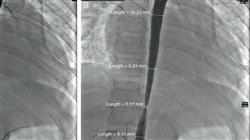

Por último, serão examinadas técnicas avançadas de imagem, como a angiografia rotacional e outras tecnologias emergentes de imagem, aplicadas a cardiopatias congênitas em adolescentes e adultos. Adicionalmente, o tratamento das artérias pulmonares nesses pacientes será explorado, capacitando os participantes a interpretar imagens complexas e realizar procedimentos técnicos fundamentais para tratar as cardiopatias.